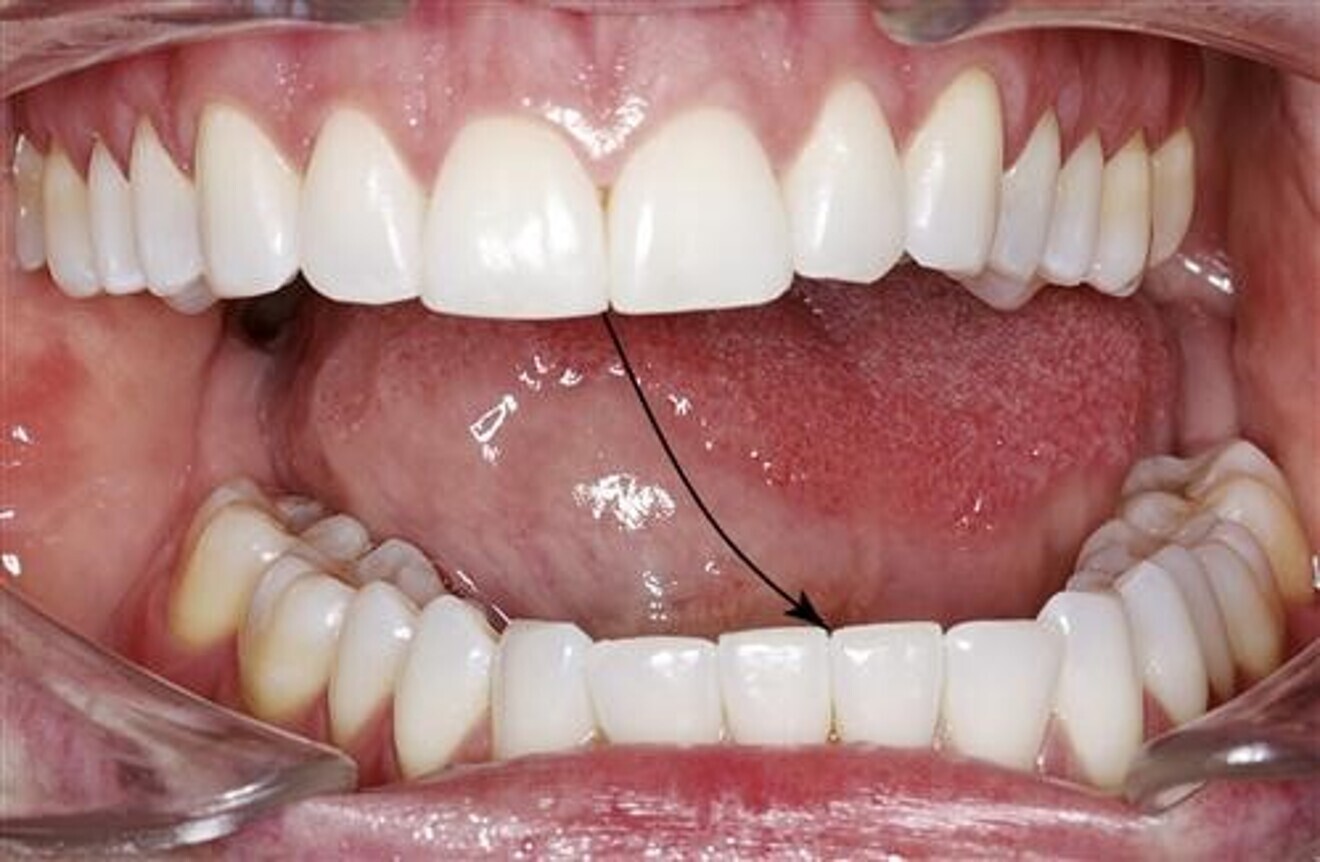

Throat obstructions: Mallampati Score and Tonsil Grading

Dentists are the gatekeepers of the airway. When we’re looking inside the mouth and doing our dental/perio charting, we’re already looking down the person’s airway. A very simple airway screening tool is checking if the tongue (Mallampati Score) or tonsils (Tonsil Grading) are blocking the throat. Just ask your patient to open wide and stick out their tongue as far as they can, then simply record their Mallampati score and Tonsil Grade.